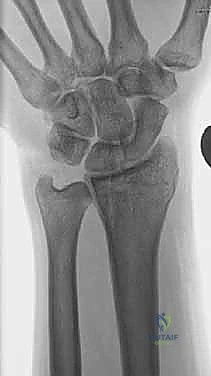

صورة طبية توضح كسر الناتئ الإبري

صورة لكسر في رأس الزند

استخدام الأشعة السينية في التشخيص

1. الأشعة السينية (X-rays): بوضعيات متعددة (أمامية خلفية، وجانبية دقيقة). الوضعية الجانبية الحقيقية (True Lateral) حاسمة لاكتشاف أي خلع جزئي في المفصل (DRUJ).